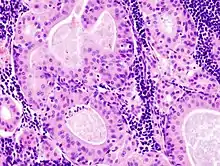

The appearance of this tumor under the microscope is unique. There are cystic spaces surrounded by two uniform rows of epithelial cells with centrally placed pyknotic nuclei. The cystic spaces have epithelium referred to as papillary infoldings that protrude into them. Additionally, the epithelium has lymphoid stroma with germinal center formation.

Histopathology of Warthin tumor in the parotid gland. Another view of Fig 1

Histopathology of Warthin tumor in the parotid gland. Higher magnification of a Fig 1